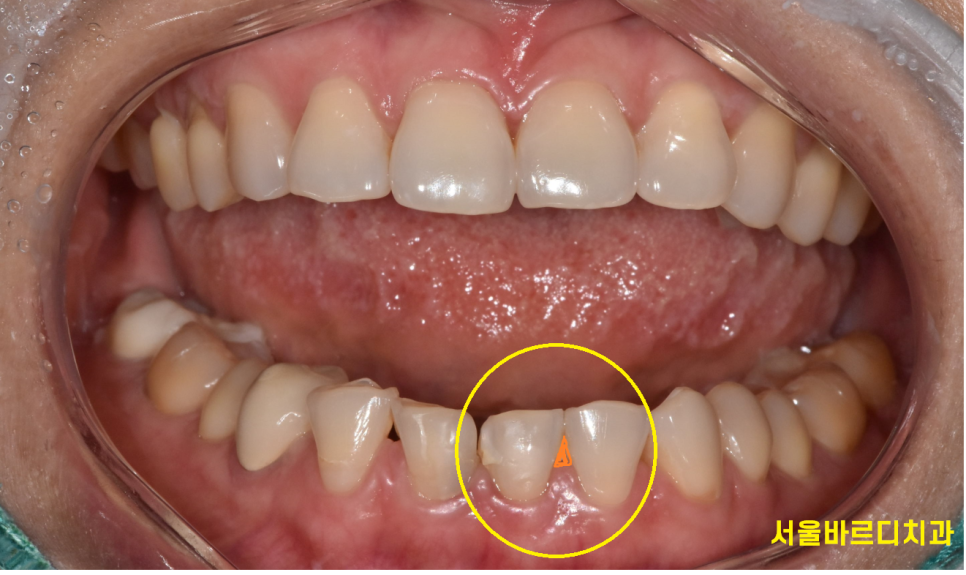

고덕동 치과 아래 앞니가 벌어져서 내원하셨는데요.

보니까 치아 주변으로 치석이 쌓여있네요~

1차적으로 치석부터 제거하고 재평가를 해보았습니다.

1)아래 앞니 벌어짐을 해결

- 색상을 밝게

2가지를 원하셨습니다.

230523

벌어진 아래 앞니 2개만 라미네이트를 우선 진행

주황색으로 표시한 부분을 사이가 보이지 않게

최대한 메꿔드리기로 하였습니다.

그리고 전반적으로 약간 회백색을 띄는 치아 색깔을

미백으로 하얗게 만들기로 상담해드렸습니다.